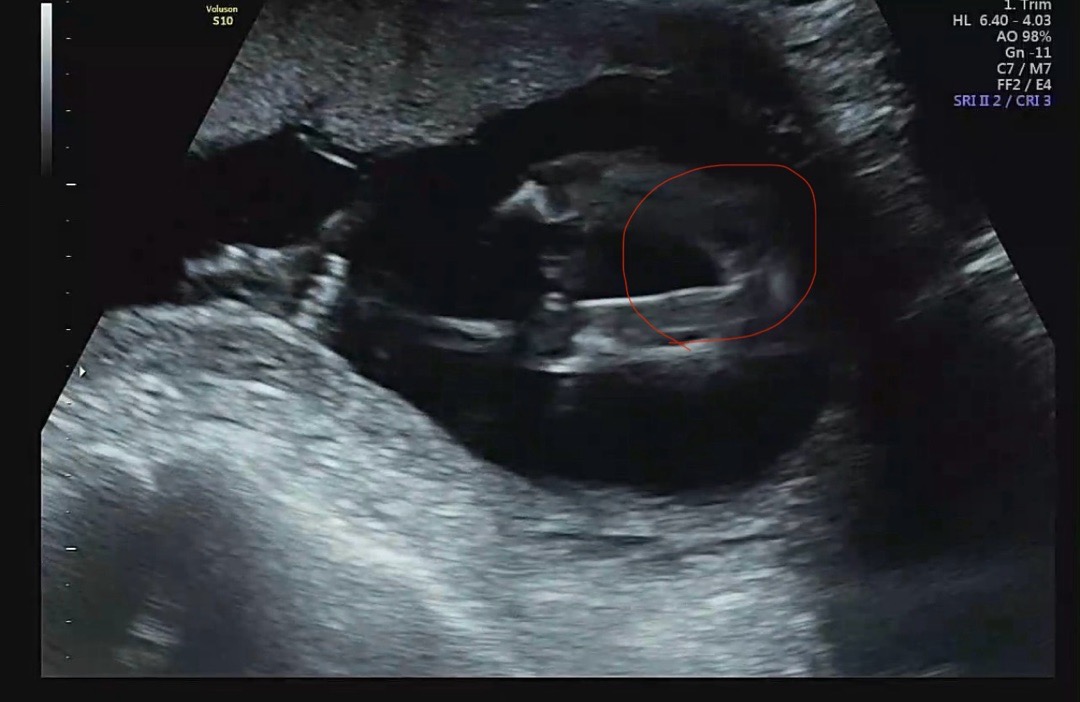

동그라미 잇는곳이 다리사이인데 계속 같이 보는데 암 것도 없긴 하던데 딸이라거 하시는데 주변에 딸인줄 알고 낳앗는데 아들이였다는 지인이 몇있어서 반전있을까요 21주차에 확인하면 100퍼센트일까용?

원래 생식기가 남녀 모두 약간 볼록한듯 똑같이 있다가 남자면 점점 도드라지면서 생식기형태를 갖추게 되고, 여자면 볼록한것이 점점 매끈(?)해지면서 아무것도 안보이게 되는 건데 다소 늦게 남자 생식기가 형성되는 경우가 있기 때문에 여자인줄 알았다가 남자였다는 일명 ‘성별반전’이라는게 있는 거에요~ 그래서 통상적으로 정확한 시기는 20-24주, 100%라 함은 24주 이후라고 생각하시면 될것같아요.